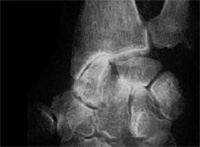

Le carpe bossu se définit par l’existence d’une tuméfaction dure, située à la base du 2e et 3e métacarpiens. Cette tuméfaction peut être acquise, plus fréquente chez la femme que l’homme, du côté dominant et survenant vers la quarantaine, dégénérescence arthrosique dont le « bec de perroquet » est palpable sous la peau. Certaines professions exposées ou certains sport (la boxe…) peuvent entraîner cette pathologie plus précocement. Cette lésion peut être parfois congénitale, en raison de l’ossification d’un noyau accessoire local, qui deviendrait douloureux (pour des raisons inconnues).

Le motif de consultation est soit « esthétique » ; c’est l’aspect de la bosse qui dérange la patiente. Cette tuméfaction peut être aussi douloureuse par le conflit mécanique qu’elle entraîne avec les extenseurs voisins. Un kyste arthro-synovial peut aussi être associé. Les patients peuvent aussi consulter pour récidive d’un kyste synovial déjà opéré.

Une radiographie standard face et surtout profil strict fait le diagnostic.